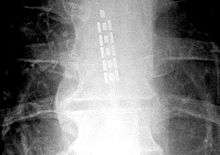

![]() Anterior view X-ray of a spinal cord stimulator (SCS) implanted in the thoracic spine |